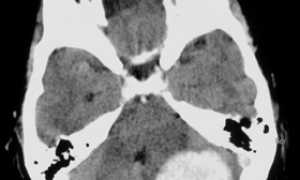

Парализация правой стороны происходит при имеющемся очаге поражения, выражающихся в форме кровоизлияния и ишемического инсульта, он локализируется в левом полушарии головного мозга пациента.

Возникновению правосторонней парализации способствует перенесенный человеком инсульт, очаг поражения которого определяется в левополушарной области мозга. Она характеризуется частичным, либо же и вовсе полным параличом половины человеческого тела, сопровождающимся нарушением чувствительности и изменением мышечного тонуса.

При возникновении локализации очага поражения во внутренней капсуле левополушарной стороны мозга (район заднего бедра) у человека может сформироваться в остром периоде такая форма паралича, как правосторонняя гемиплегия (полная парализация).

В таком случае будет отсутствовать движение в верхней и нижней конечностях, находящихся с правой стороны. Данная форма связана с потерей всех видов чувствительности или гемигипестензией и нарушением зрительной функции, проявляющимся в виде двухсторонней слепоты в половине поля зрения — гемианопсией. В этой форме инсульта специалистами выделяются: